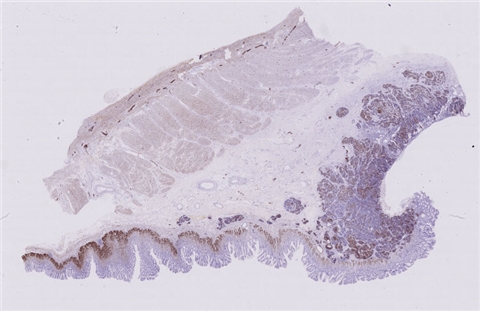

免疫组化: 2002032-004#:CgA(弱+)、syn(+)、CD56(+)、 2002032-002#:CK(+)、TTF-1(+)、CD34 +、SMA(-)